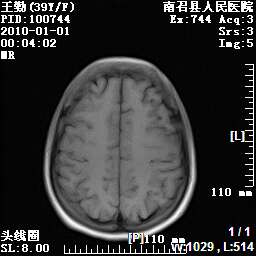

以下是引用随光逐影在2010-1-22 9:03:00的发言:[br]考虑左侧中颅窝(蝶骨翼区)脑膜瘤侵犯蝶骨翼并突入左侧眼眶。

以下是引用水过无痕在2010-1-22 14:55:00的发言:[br]一、定位:颅外占位;二、定性:恶性可能性大;三、组织来源:来源于左侧眼外直肌或其他部位;考虑为:横纹肌肉瘤>转移瘤>脑膜瘤.